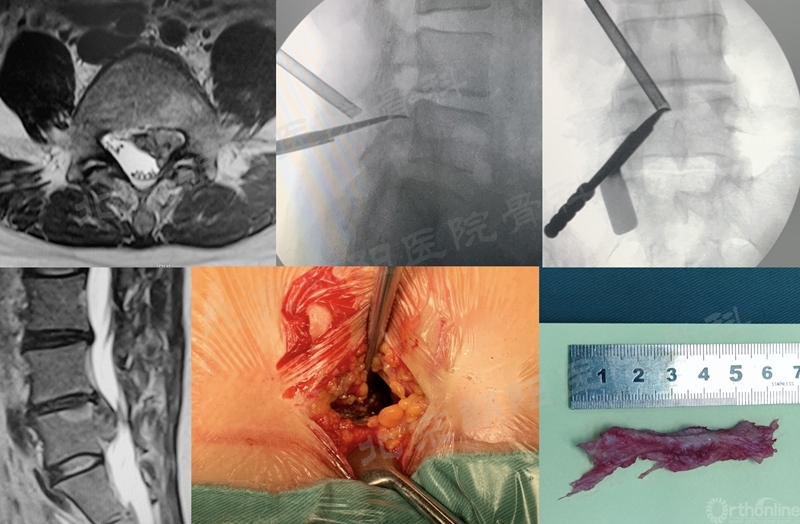

3、 硬膜损伤

#2例UBE,游离型LDH,未做好充分的上关节突内侧减压,误把硬膜当做突出的间盘,导致硬膜撕裂。及时转切开减压,取出大块髓核组织。

#10例UBE, L4/5 LSS。

#12例UBE,PLIF术后8年L3/4 ASD。

#9例UBE,ADS合并L4/5LDH。